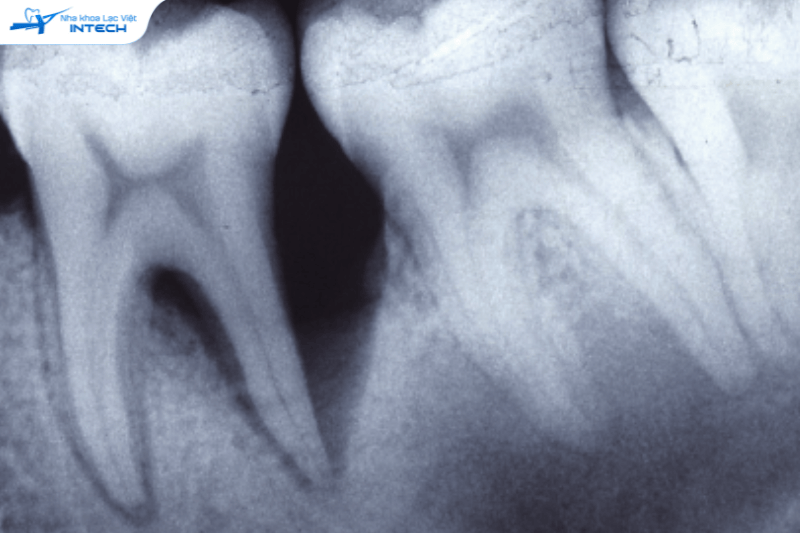

1. Biến chứng niềng răng Bật chân răng ra khỏi xương ổ răng

Đây là một trong những tác hại của niềng răng nặng nề và đáng lo ngại nhất. Bình thường, chân răng của bạn phải nằm gọn theo trục của xương hàm. Tuy nhiên, nếu bác sĩ sử dụng lực quá mạnh, hoặc kiểm soát lực không tốt trong quá trình niềng răng, chân răng có thể bị bật ra khỏi vị trí này. Ngoài ra, việc sử dụng các khí cụ kém chất lượng cũng là một nguyên nhân gây ra tình trạng này. Khi đó, chóp răng có thể trồi hẳn ra ngoài.

bật chân răng khỏi xương khi niềng

Nếu không kiểm soát lực tốt sẽ dẫn đến biến chứng bật chân răng khỏi xương

Hậu quả bật chân răng khi niềng

Hậu quả của biến chứng này rất nghiêm trọng. Việc khắc phục vô cùng nan giải, tỉ lệ thành công chỉ khoảng 30%. Với 70% trường hợp còn lại, bạn sẽ buộc phải nhổ bỏ răng và thay thế bằng cấy ghép Implant. Điều này không chỉ gây tốn kém về chi phí mà còn mất nhiều thời gian và công sức.

Dấu hiệu nhận biết

Để chẩn đoán chính xác, bác sĩ cần chụp phim CT Cone Beam. Tuy nhiên, bạn có thể nhận biết sớm tại nhà qua một số dấu hiệu:

• Răng bị cụp vào trong: Bạn thấy răng của mình tự nhiên bị cụp vào, đặc biệt là khi cắn hai hàm răng lại với nhau.

• Khớp cắn nấp hộp: Khi bạn cắn lại, bạn không thể nhìn thấy răng hàm dưới.

• Sờ thấy chóp răng nhô ra: Bạn có thể sờ thấy một cục cứng nhô ra ở phần lợi phía trên chân răng. Dù vậy, dấu hiệu này cũng có thể là do xương ổ răng quá phát, nên bạn cần thăm khám bác sĩ để có kết luận chính xác.